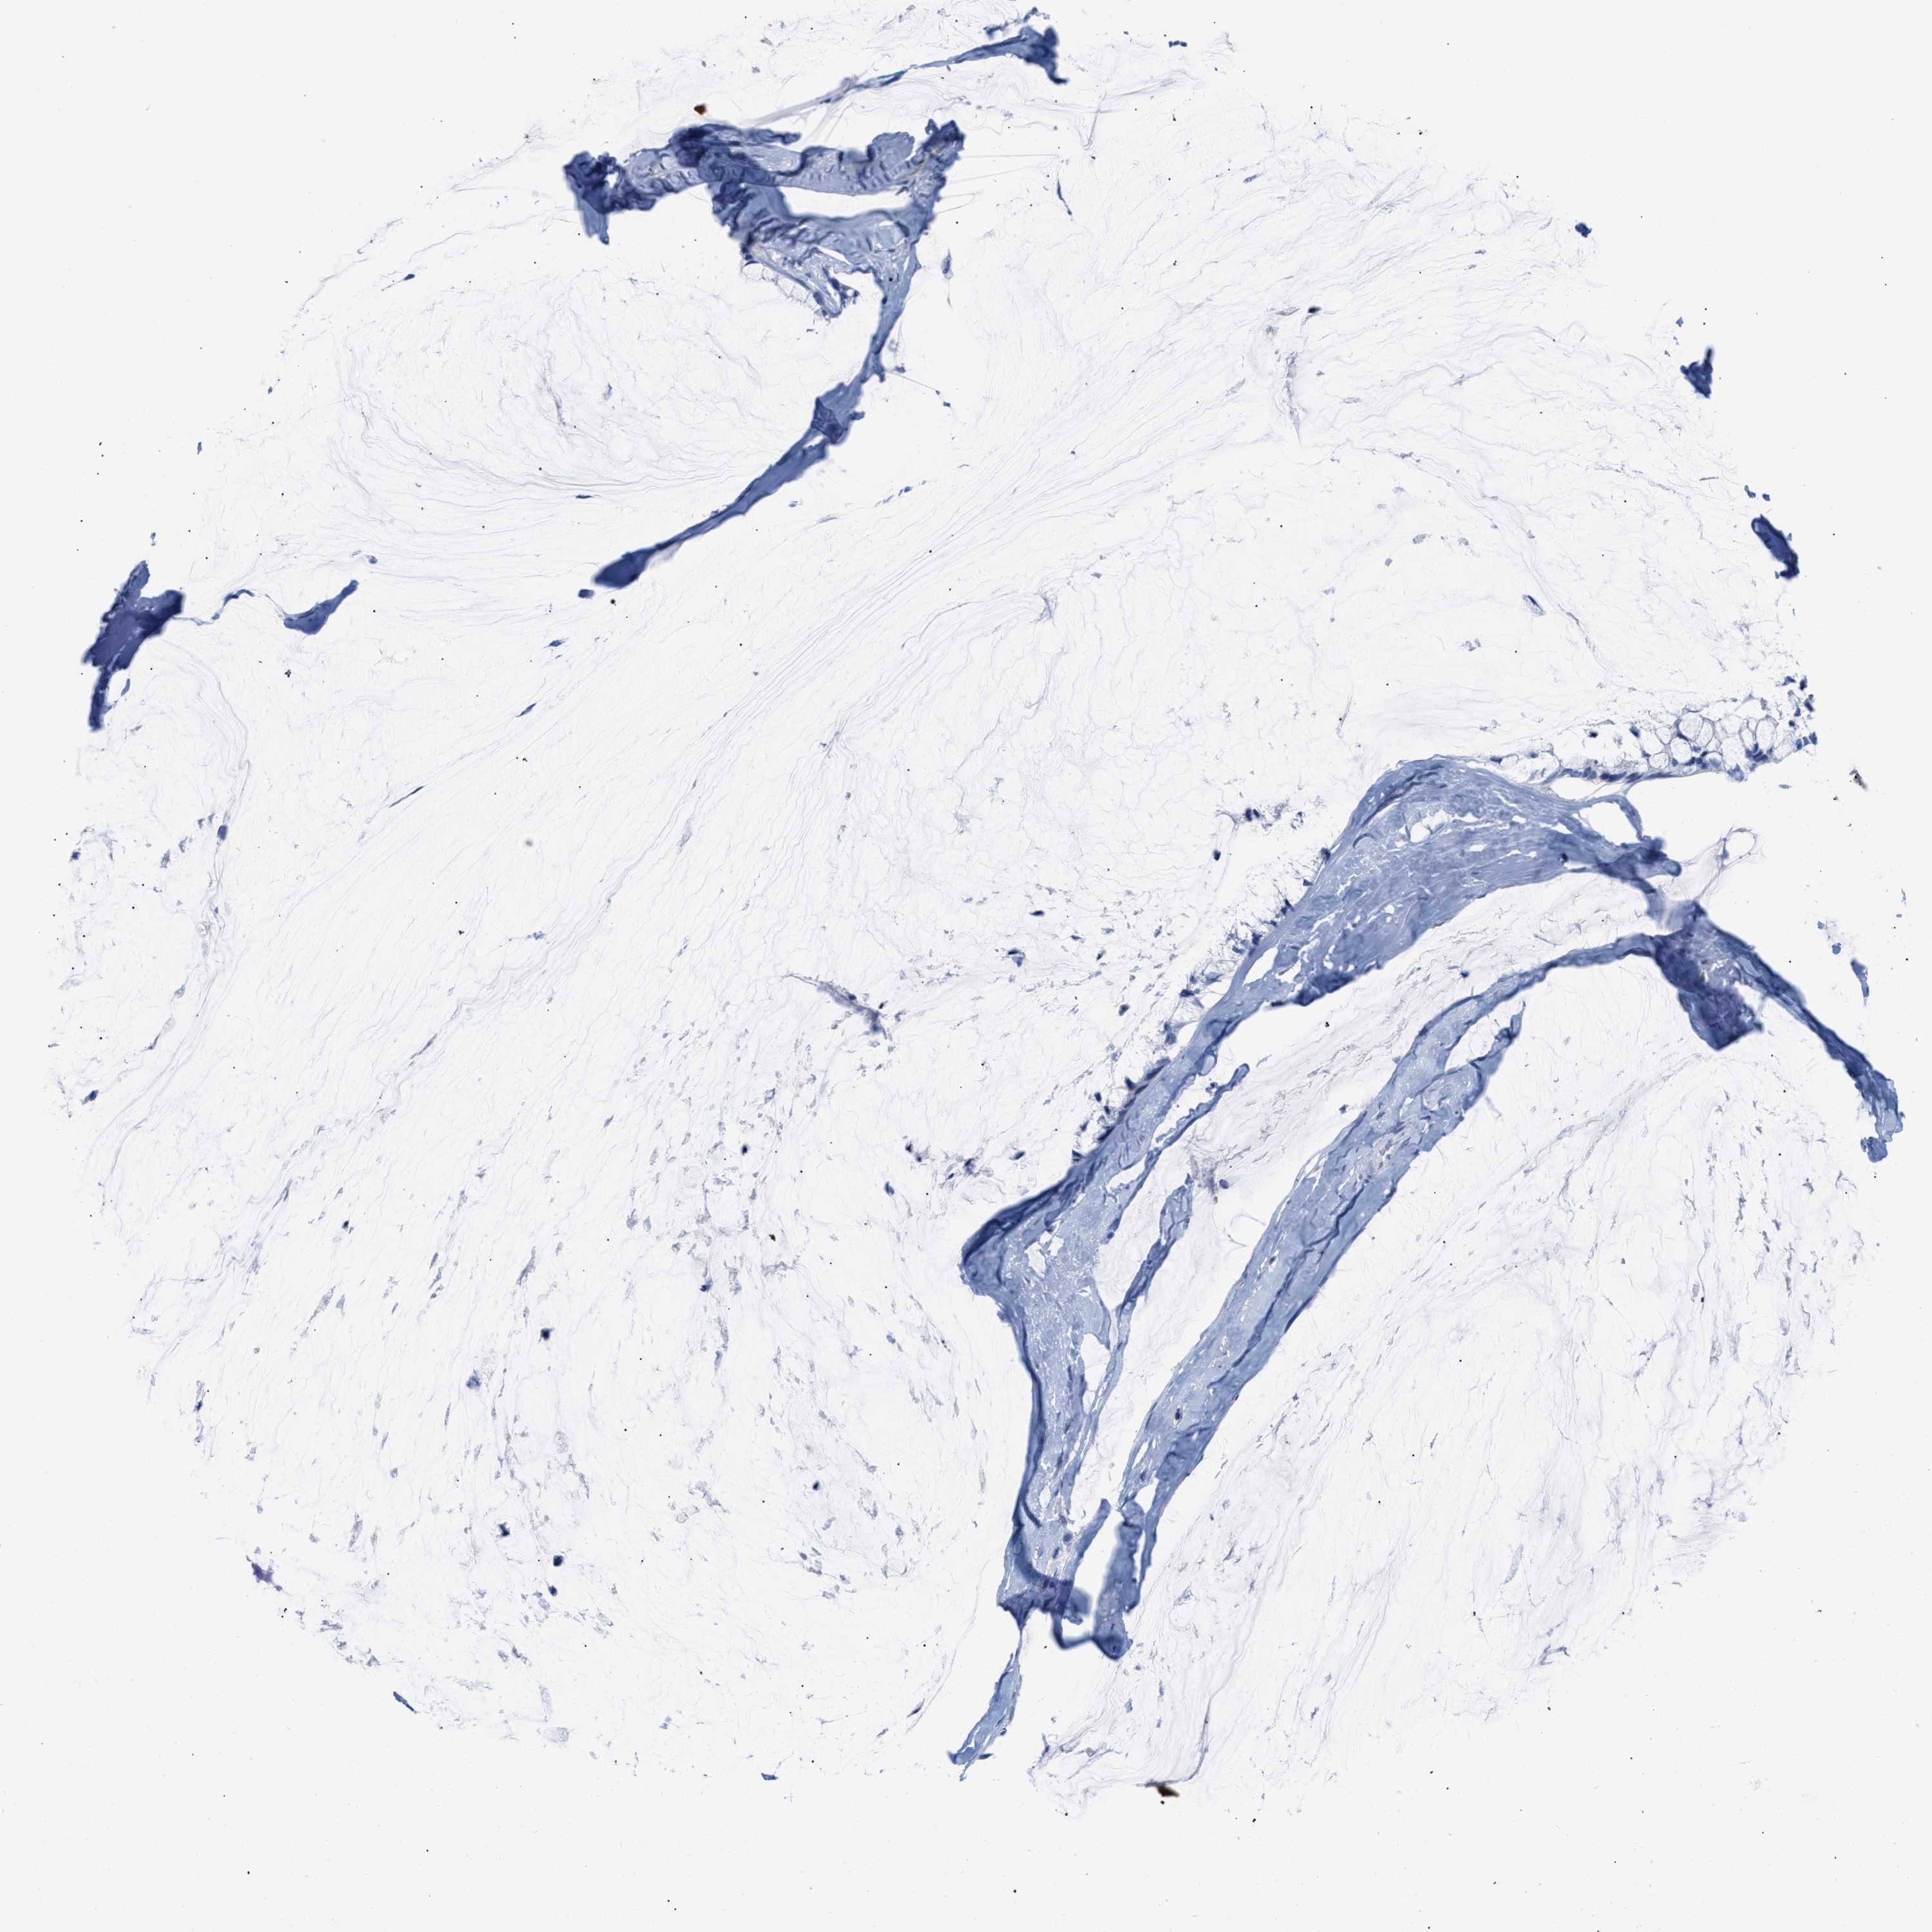

OVARIAN CANCER - Protein expressioni

A mouse-over function shows sample information and annotation data. Click on an image to view it in a full screen mode. Samples can be filtered based on level of antibody staining by selecting one or several of the following categories: high, medium, low and not detected. The assay and annotation is described here.

Note that samples used for immunohistochemistry by the Human Protein Atlas do not correspond to samples in the TCGA dataset.

Antibody stainingi

Antibody staining in the annotated cell types in the current human tissue is reported as not detected, low, medium, or high, based on conventional immunohistochemistry profiling in selected tissues. This score is based on the combination of the staining intensity and fraction of stained cells.

Each image is clickable and will lead to virtual microscopy that enables deeper exploration of all samples and also displays staining intensity scores, fraction scores and subcellular localization as well as patient and tissue information for each sample.

Antibody HPA018467

Antibody CAB005247

Cystadenocarcinoma, serous, NOS

Carcinoma, endometroid

Cystadenocarcinoma, mucinous, NOS

Carcinoma, NOS